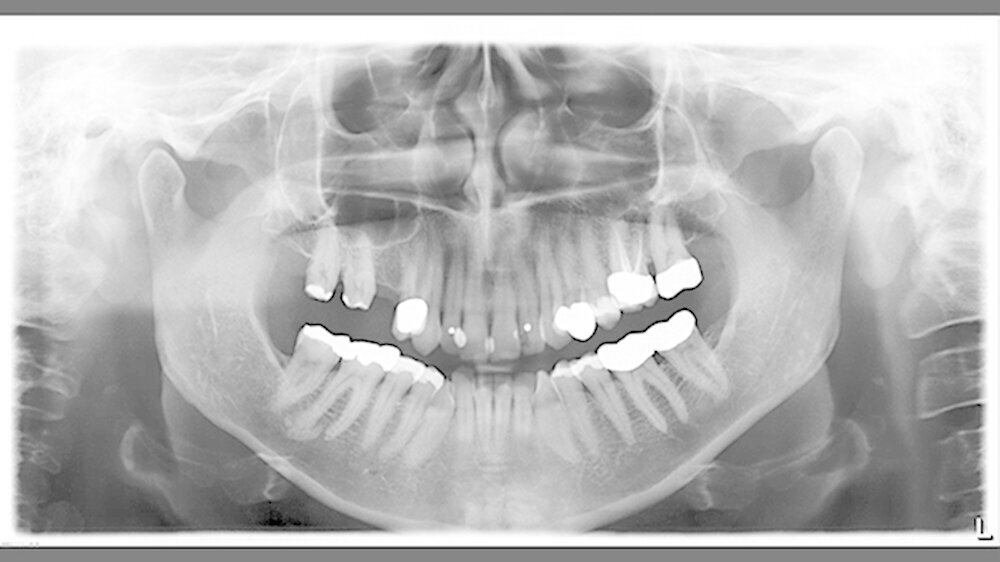

Auf dem Orthopanthomogramm stellte sich an der distalen Wurzel des Zahns 46 eine halbmondförmige, etwa zehn Millimeter große röntgenopake Verschattung dar. Dazu war eine etwa drei Millimeter große eiförmige dorsal davon gelegene kleine Auftreibung zu sehen, die mit der Wurzelspitze in Verbindung zu stehen schien. Die Vitalitätsprüfung des Zahns 46 war eindeutig positiv. Die Verdachtsdiagnose lautete „sklerosierende Ostitis 46“.

Aufgrund der Symptomlosigkeit und der benignen Prognose wurde von einer Therapie zu diesem Zeitpunkt abgesehen. Wir vereinbarten mit der Patientin allerdings eine weitere grobmaschige Röntgenverlaufskontrolle.